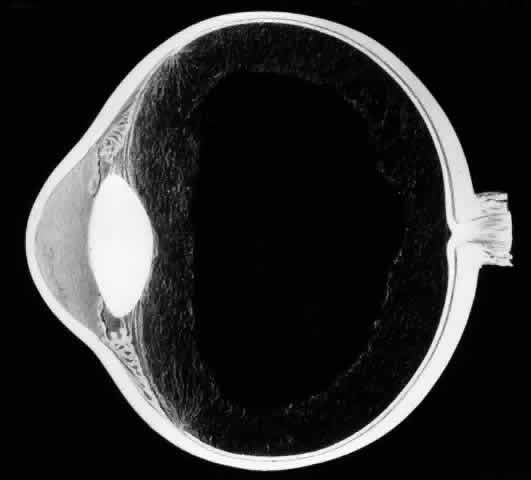

The outer surface of the inverted retinal flap (Fig. 1) should be examined for signs of epiretinal tissue proliferation, which may produce radial or star-shaped folds in the flap. Vitreous base traction produces detachment of the anterior edge of the giant tear and the pars plana epithelium anterior to it in 82% of giant retinal tears.9 It is important to identify and treat detachment of the pars plana epithelium that extends beyond the ends of the giant tear because leakage of subretinal fluid beneath it can be a potential source of postoperative posterior retinal detachment.

Fig. 1. Superior giant retinal tear extending from 9:30 to 3:30 meridian. The retina is torn at the posterior border of the vitreous base. Posterior retinal flap is invertd over the optic disc. Anterior edges of giant tear, ora serrata, and pars plana are detached from the 9:30 to 3:00 meridians as a result of vitreous base traction.